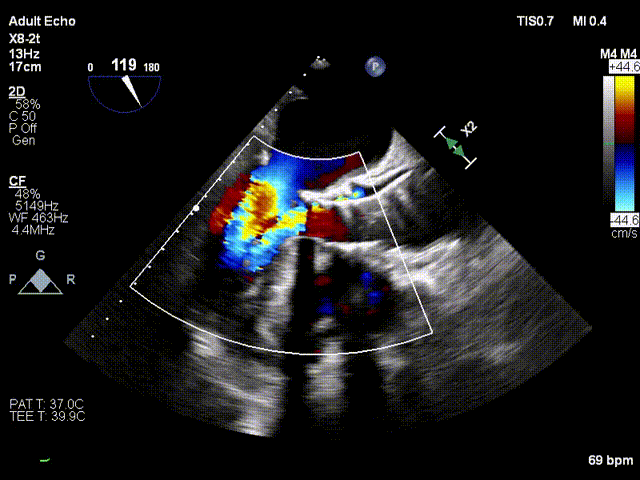

术中超声评价:跨瓣流速1.6m/s,平均跨瓣压差5mmHg,可见少量瓣周漏。